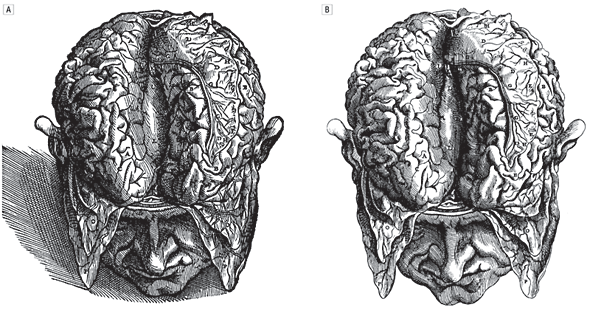

la neuronavigation est très utile dans les tumeurs de la convexité, surtout de petite taille et à proximité de la région centrale ; il est illusoire de vouloir reconnaitre les sillons corticaux, surtout lorsque l’anatomie est modifiée par la tumeur. par ailleurs l’imagerie peut être trompeuse en faisant croire que la tumeur sera visible dès l’ouverture durale alors qu’elle est sous-corticale. inversement, la neuronavigation n’est pas indispensable lorsqu’il existe des repères anatomiques fiables : suture coronale, vallée sylvienne, sillon péri-calleux, structures de la base.

la résection est guidée par l’anatomie, la neuronavigation, et parfois des modifications de la voûte (soufflure) ou du cortex (coloration, déplissement, induration).

chaque fois que possible, la chirurgie est sulcale, ouvrant le sillon bordant la tumeur et respectant les vaisseaux à destinée du gyrus adjacent. lorsque le plan pial se sépare bien de la lésion (en particulier dans les dysplasies), la dissection sous-piale permet au mieux de respecter le gyrus adjacent.